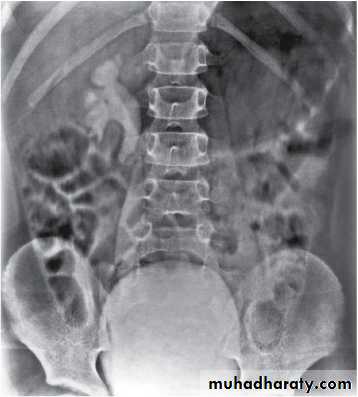

Grading of VUR

The degree of reflux is graded I–V.

Grading is based on the appearance of contrast agent in the collecting system during voiding cystourethrography (VCUG(.

The VCUG:

the definitive examination

to diagnose and grade reflux and establish reversible causes

must include a voiding phase:

in some cases, reflux may be seen only during the elevated intravesical pressures associated with micturition.

in visualizing the urethra, may allow the diagnosis of outflow obstruction to be made (e.g., posterior urethral valves).